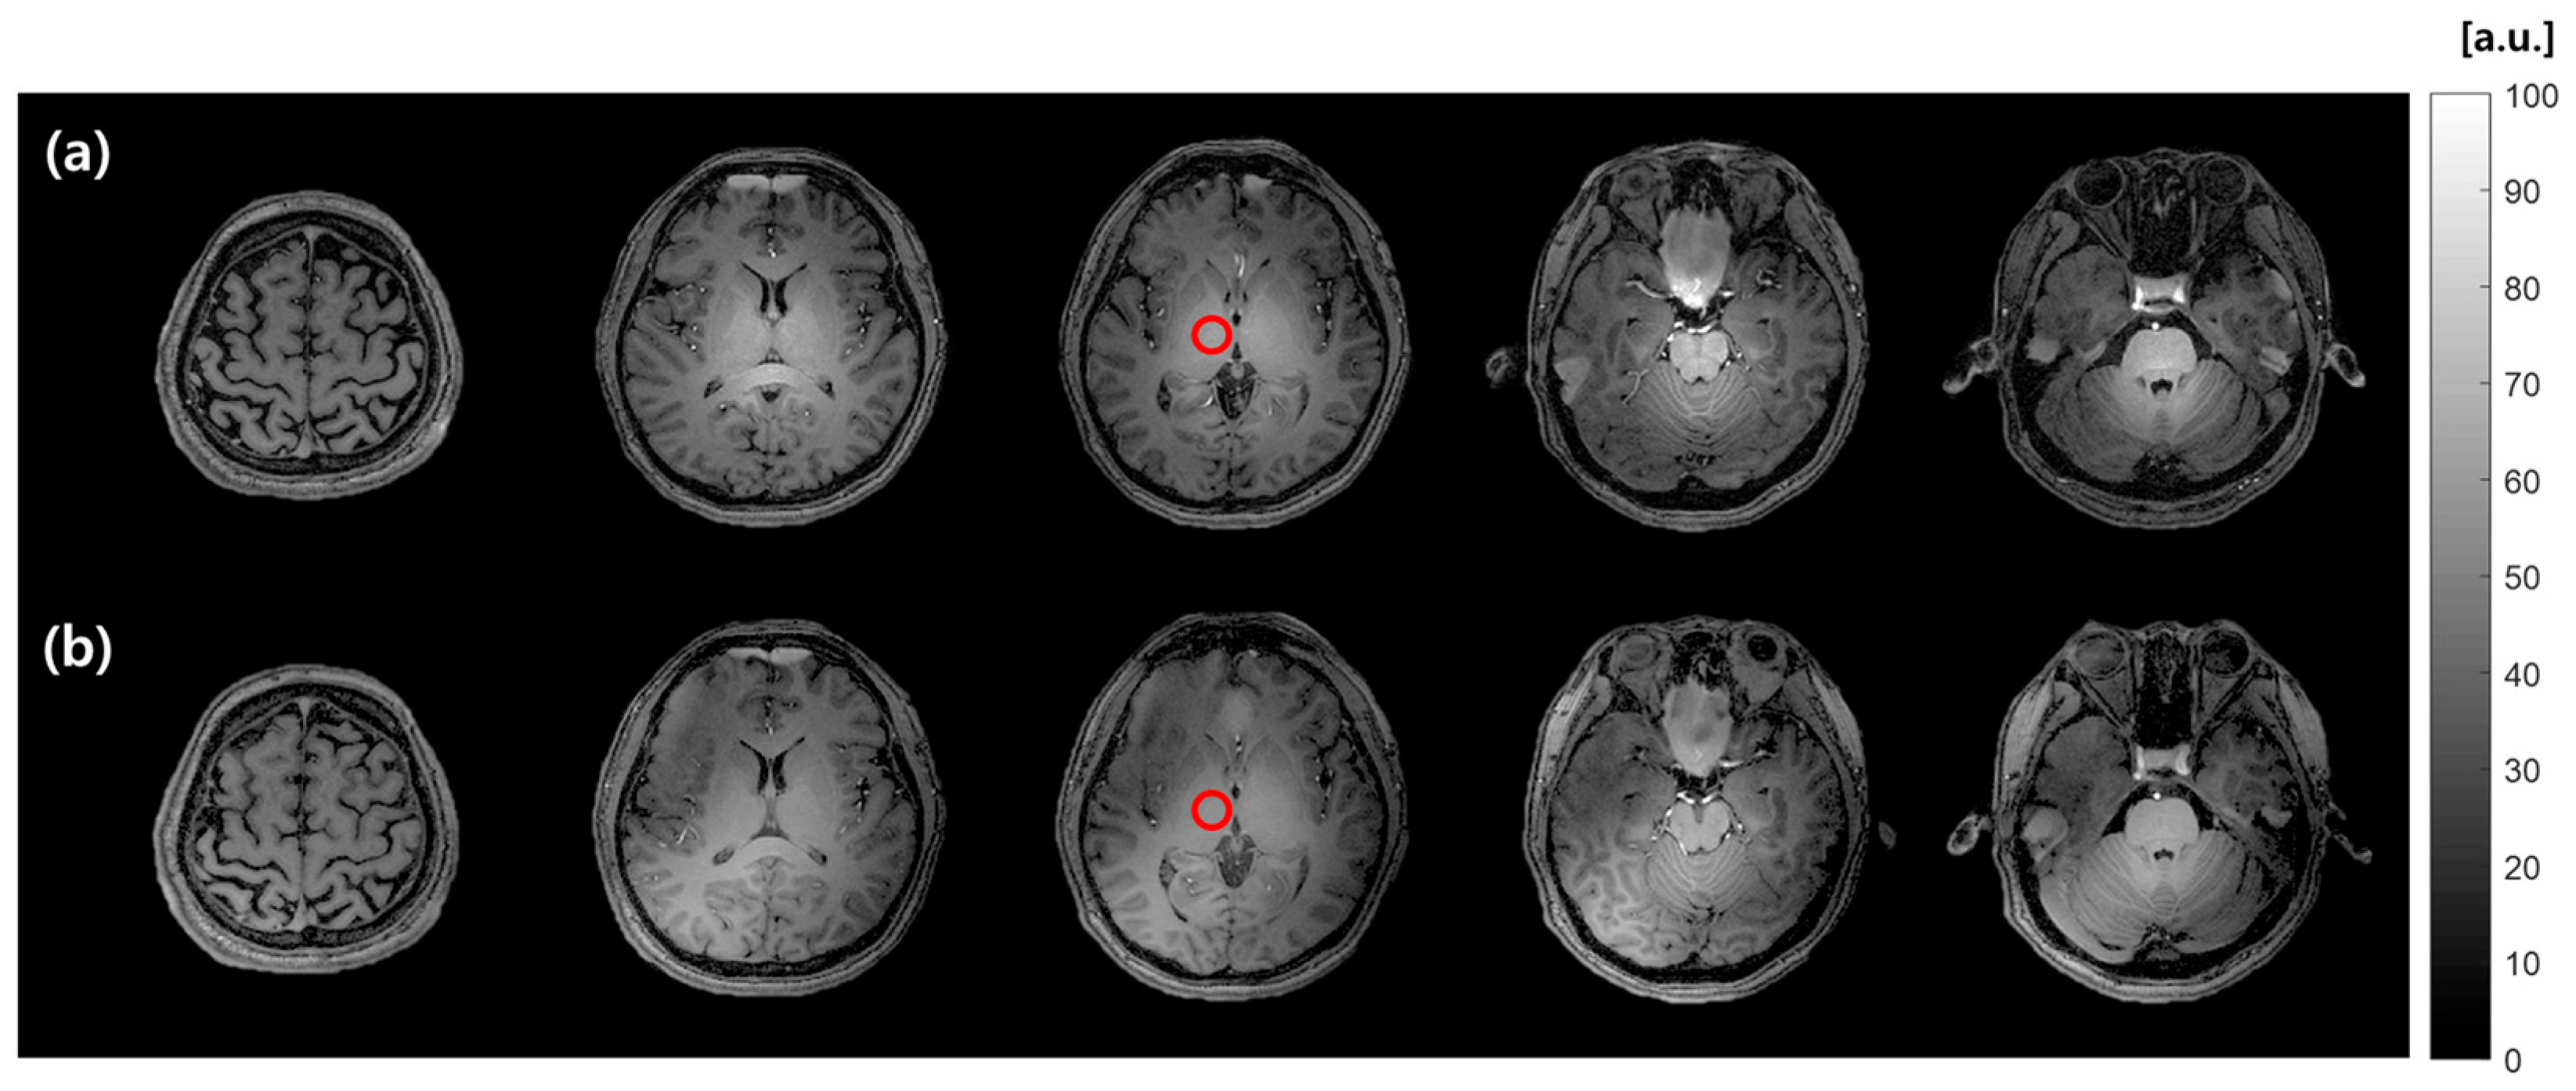

3.3. MR Imaging Experiments

| Sequence | Dual-TR (AFI) | T1-weighted MPRAGE | UTE (DAM) | UTE |

| Nominal FA (°) | 60 | 7 | 45 and 90 | 32 |

| TE/TR (ms) | 3.9/20 and 120 | 2.6/5.5 | 0.19/120 | 0.19/100 |

| FOV (mm3) | 240 × 240 × 240 | 240 × 240 × 240 | 240 × 240 × 240 | 240 × 240 × 240 |

| Acquisition matrix | 120 × 120 | 240 × 240 | - | - |

| Reconstruction matrix | 120 × 120 | 240 × 240 | 68 × 68 | 68 × 68 |

| Image resolution (mm2) | 2 × 2 | 1 × 1 | 3.5 × 3.5 | 3.5 × 3.5 |

| Slice thickness (mm) | 8 | 1 | 8 | 8 |

| Average | 1 | 1 | 1 | 3 |

| Scan time (min) | 2 min 47 s | 6 min 6 s | 6 min 1 s | 30 min |